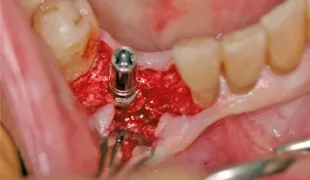

Aufgrund einer fortgeschrittenen parodontalen Erkrankung und eines schweren Knochenverlustes rund um den infizierten Zahn, musste der obere Prämolar des Patienten extrahiert werden. Im posterioren Oberkiefer wurde ein intraalveolärer Knochendefekt der Klasse I diagnostiziert, ohne eine Dehiszenz oder einen Fenestrationsdefekt vorzuweisen.

Dieser Patient wurde bereits im Jahr 1991 behandelt. Der Fall zeigt eine der ersten klinischen Anwendungen von Geistlich Bio-Oss Collagen. Aufgrund des intraalveolären Knochendefekts wurde eine Frühimplantation mit gleichzeitiger Augmentation durchgeführt. Die Implantation wurde 6 Wochen nach Extraktion des Prämolars vorgenommen. In der postoperativen Phase erfolgte eine unauffällige Weichgewebeheilung nach Extraktion. Für die Implantatinsertion wurde der Frühimplantationsansatz mit einer Heilungsphase von 6 Wochen gewählt. Die Knochenaugmentation wurde gleichzeitig mit der Implantatinsertion durchgeführt. Das Implantat wurde nach der Lappenpräparation an einer Stelle mit einem schweren Knochendefekt eingesetzt.

Für den Knochenaufbau wurde Geistlich Bio-Oss Collagen in den Defekt appliziert und nach der Augmentation die Eingriffsstelle mit einem Kollagenvlies abgedeckt. Weitere 6 Monate nach dem Eingriff wurde die endgültige Kronenrestauration eingesetzt. Bei der weiteren Nachuntersuchung nach nunmehr 25 Jahren zeigte die Röntgenaufnahme ein stabiles Implantatlager und das klinische Bild bei der Nachkontrolle einen ästhetischen Zahnstatus.